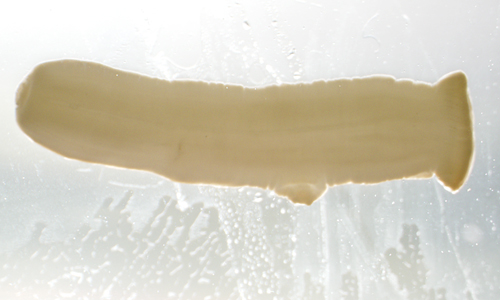

A 26-year-old female presented at a local hospital with severe pain and bloody discharge from the ear. The symptoms started while on a returning flight from vacation in Central America. The patient explained that while on vacation she visited a local physician to have a fly removed from her ear canal.